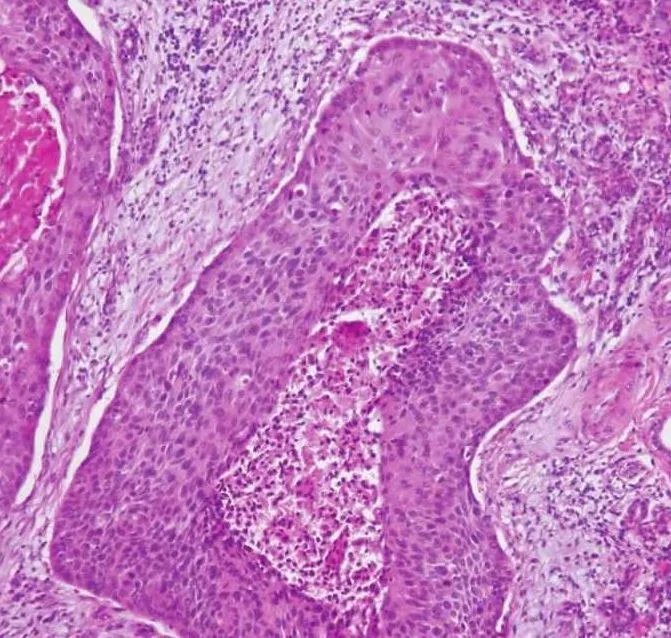

的有关信息介绍如下:概述唾液腺鳞状细胞癌(squamous cell carcinoma,SCC)又称表皮样癌,是指原发于唾液腺的鳞状细胞癌,极为少见。国内上海的6982例唾液腺肿瘤研究中,发生在大唾液腺者为5002例,其中恶性1008例,包括鳞状细胞癌鳞癌36例(占大唾液腺肿瘤0.7%;占大唾液腺癌3.6%),其中腮腺29例、下颌下腺7例。国内7所口腔医学院校36944例唾液腺肿瘤中有原发性鳞状细胞癌102例,占0.3%。其组织发生可来源于排泄管的基底细胞或唾液腺导管的鳞状化生。病因因素可能与辐射暴露相关。唾液腺原发性鳞状细胞癌是排除性诊断,即诊断前首先应排除来自于上面部皮肤、外听道、头皮和有时包括上呼吸消化道的转移性癌。也应排除外听道和皮肤鳞状细胞癌的直接扩展,还要排除其他腮腺肿瘤如高级别黏液表皮样癌、有鳞状分化的唾液腺导管癌(还包括多形性腺瘤恶变为鳞状细胞癌者)。对于下下颌下腺的原发性鳞状细胞癌应首先排除口底鳞状细胞癌的直接扩散,此部位转移性癌罕见。由于报道上的偏差和数据结构的不同,从文献上很难得到原发性大唾液腺鳞状细胞癌的发病率。多数文献包括了转移性和其他部位浸润至腺体的鳞状细胞癌,因此不同文献报道的发病率差异很大。临床表现此瘤主要发生于腮腺和下颌下腺,腮腺多见。罕见情况下鳞状细胞癌可来自于Stensens管或舌下腺。小唾液腺偶尔也发生鳞状细胞癌,但由于很容易与口腔黏膜癌混淆,难以确定。男性较多见,且多见于中年以上,50~70岁为发病高峰。肿物生长较快,病期短,多在半年以内,无症状或伴有疼痛。腮腺肿瘤多出现面瘫,皮肤表面可出现溃疡,浸润性生长,边界不清,与皮肤和/深部软组织固定。常发生区域淋巴结转移。X线唾液腺造影显示导管中断,腺泡充盈缺乏,碘油外溢。在腭部者X线片可见溶骨性破坏、界限不清的肿块。发生在唾液腺导管处的肿瘤由于部分或全部阻塞导管,可导致腮腺间断性疼痛性腮腺肿大,类似于炎症表现。临床上可误诊。大体病理肉眼见肿瘤形态不规则,多大于3cm、质地较硬,无包膜,与周围组织无界限。剖面实质性,灰白色,易碎。临床表现此瘤主要发生于腮腺和下颌下腺,腮腺多见。罕见情况下鳞状细胞癌可来自于Stensen's管或舌下腺。小唾液腺偶尔也发生鳞状细胞癌,但由于很容易与口腔黏膜癌混淆,难以确定。男性较多见,且多见于中年以上,50~70岁为发病高峰。肿物生长较快,病期短,多在半年以内,无症状或伴有疼痛。腮腺肿瘤多出现面瘫,皮肤表面可出现溃疡,浸润性生长,边界不清,与皮肤和/深部软组织固定。常发生区域淋巴结转移。X线唾液腺造影显示导管中断,腺泡充盈缺乏,碘油外溢。在腭部者X线片可见溶骨性破坏、界限不清的肿块。发生在唾液腺导管处的肿瘤由于部分或全部阻塞导管,可导致腮腺间断性疼痛性腮腺肿大,类似于炎症表现。临床上可误诊。大体病理肉眼见肿瘤形态不规则,多大于3cm、质地较硬,无包膜,与周围组织无界限。剖面实质性,灰白色,易碎。组织病理镜下表现与黏膜上皮发生的鳞状细胞癌相同。有时可见唾液腺导管的原位癌样的改变(图7-276)。浸润癌为增生的鳞状上皮团块,细胞大小不等,有核浓染及核分裂像,有的细胞巢可见角化珠或细胞间桥,根据细胞的分化程度,可分为高、中及低度分化(图7-277、7-278)。多为有角化的、分化较高的鳞状细胞癌,低分化者不到10%。有时可见原位导管异常增生,这种表现有助于原发性鳞状细胞癌诊断的确立。

图7-276 鳞状细胞癌A.唾液腺导管内衬上皮增生,呈原位癌表现;B.高倍镜下见肿瘤的异型性和角化珠